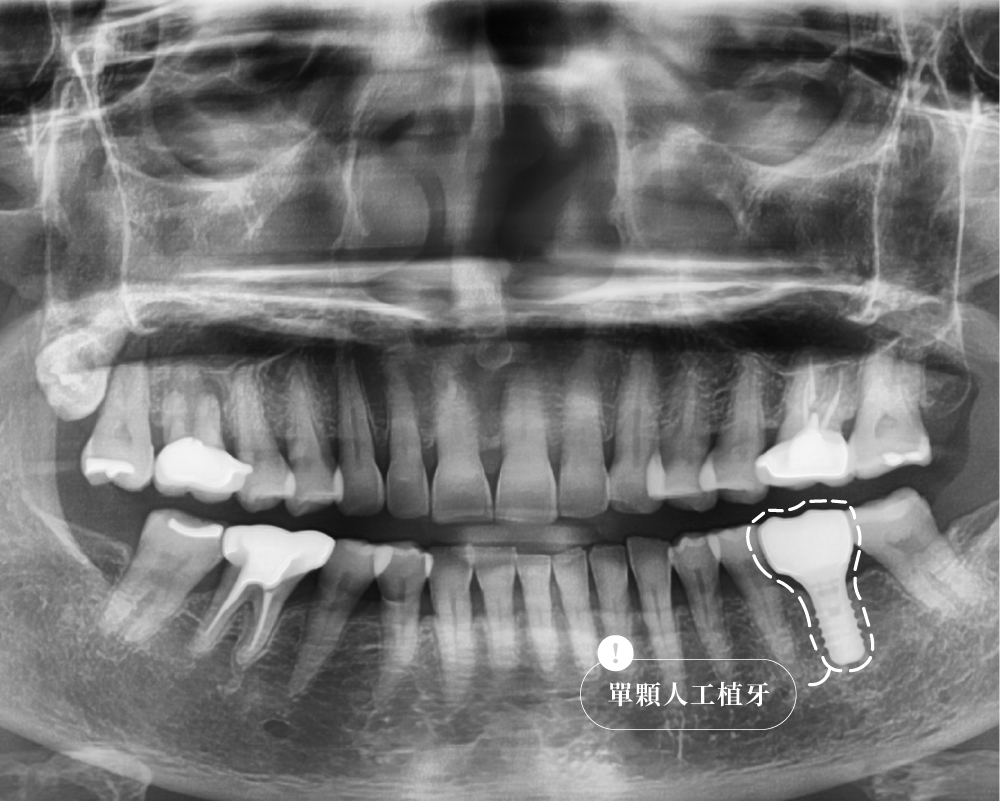

案例解析:L先生的右下第一大臼齒咬裂

治療前:牙齒疼痛疑似有牙根斷裂

治療後:單顆植牙恢復咬合